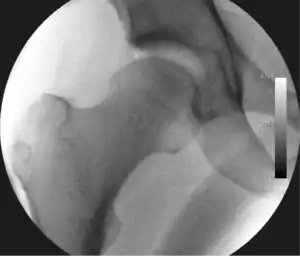

![]() Intraoperative fluoroscopic image during an arthroscopic resection of a cam lesion of the femur. The upper instrument is the arthroscope (viewing device), while the lower is the high-speed burr used for reshaping the bone. |

Standard arthroscopic treatment of symptomatic cam FAI involves debridement (resection) or repair of any labral [11] and chondral injuries [12] in the central compartment of the hip, and subsequent reshaping of the head-neck junction of the upper femur (osteochondroplasty) in the peripheral compartment [13][14] using high-speed motorised burrs that are similar in design to a dentist's drill (see fig. 9).